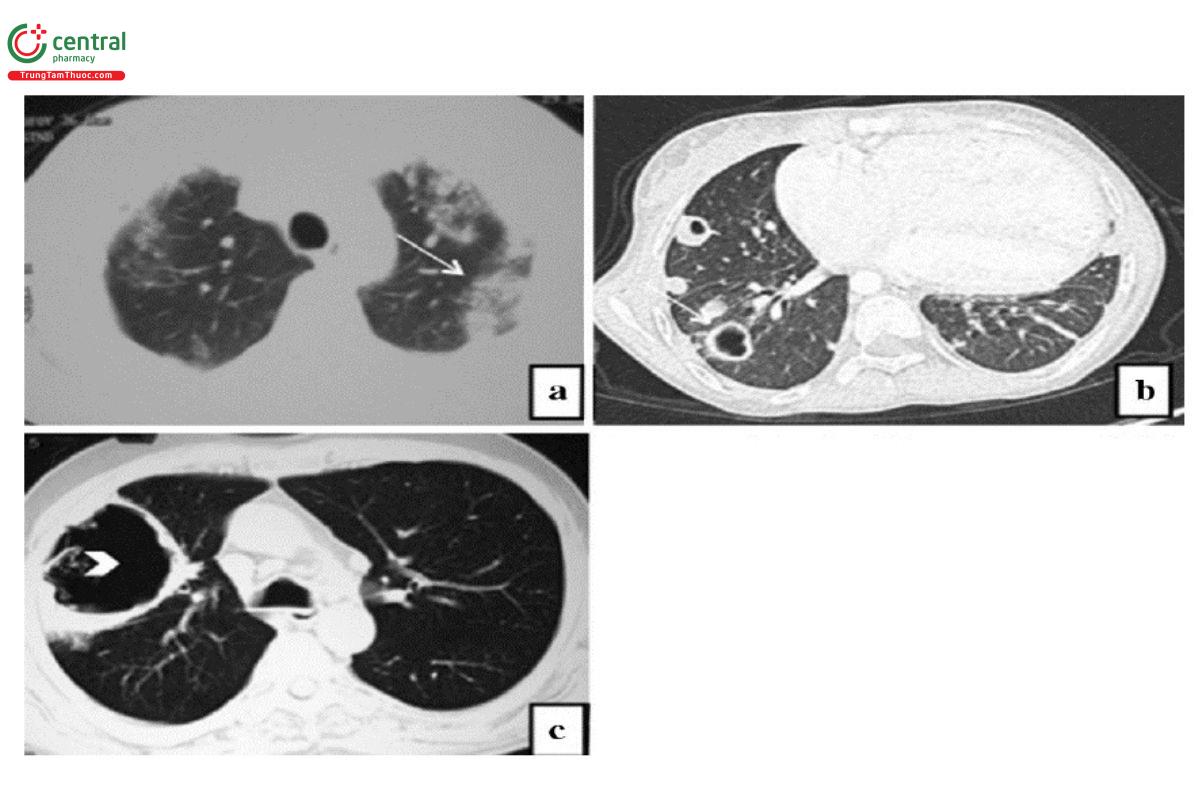

Viêm phổi do Staphylococcus aureus: Các đám đông đặc hoặc các nốt quanh phế quản, thường ở hai bên phổi, kèm theo thường có phá hủy tạo thành các ổ áp xe và tràn dịch - khí màng phổi. Khi bệnh ở giai đoạn phục hồi, có xu hướng hình thành các hang có thành mỏng gọi là bóng khí [20, 21].

Chú thích: a) Hình ảnh các nốt mờ quanh phế quản hợp nhất thành từng đám đông đặc ở thùy trên hai bên. b) Nhiều nốt mờ với một số phá hủy tạo hang (mũi tên trắng) ở phổi phải. c) Hình ảnh hang thành mỏng, lớn (mũi tên đầu).